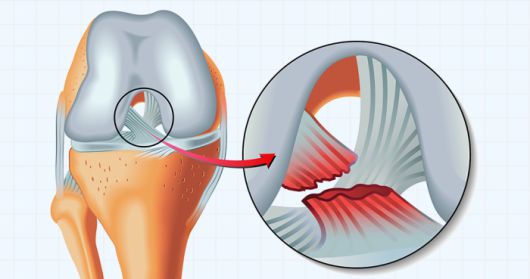

무릎 관절에 있는 '반월상 연골판’은 허벅지뼈와 종아리뼈 사이의 반달 모양의 C자형 연골조직입니다. 한쪽 무릎의 내‧외측에 각각 2개가 있으며, 허벅지뼈와 종아리뼈의 연골을 보완해 주는 역할을 합니다. 특히 다리가 비틀리는 동작에서 안정성을 확보하고, 충격을 흡수합니다.

반월상 연골판 파열의 원인에 따른 종류는 레포츠를 즐기는 젊은 사람들에게 많은 '외상성 파열’과 나이가 들면서 발생하는 '퇴행성 파열’이 있습니다.

스포츠 손상 등으로 반월상 연골판이 찢어진 '외상성 파열’은 무릎의 전방십자인대 손상과 동반해서 나타날 수도 있어서 초기인 급성기에는 무릎 부종과 통증이 심합니다. 외상성 파열 관련 세계적인 골퍼 타이거 우즈는 무릎 수술을 5회 정도 받았는데, 반월상 연골판 수술도 포함됐습니다.

반월상 연골판 손상에 따른 증상이 심하면 수술을 고려합니다. 연골판의 파열된 부분이 증상을 일으키는 경우 '연골판 부분 절제술’을 시행할 수 있습니다. 무릎의 반월상 연골판이 손상되어 파열된 부위가 관절 사이에 끼면 심한 통증이나 관절운동제한이 생길 수 있어, 이를 절제하고 정리하는 수술이 연골판 부분 절제술입니다.